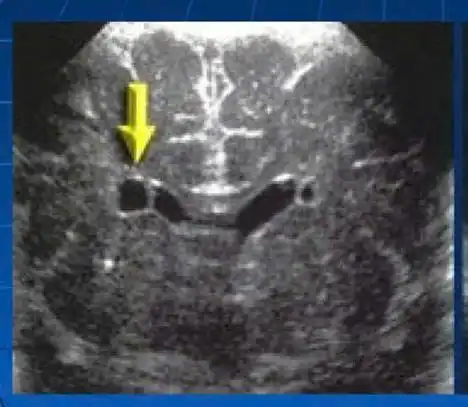

Một số hình ảnh tổn thương não phát hiện qua siêu âm thóp